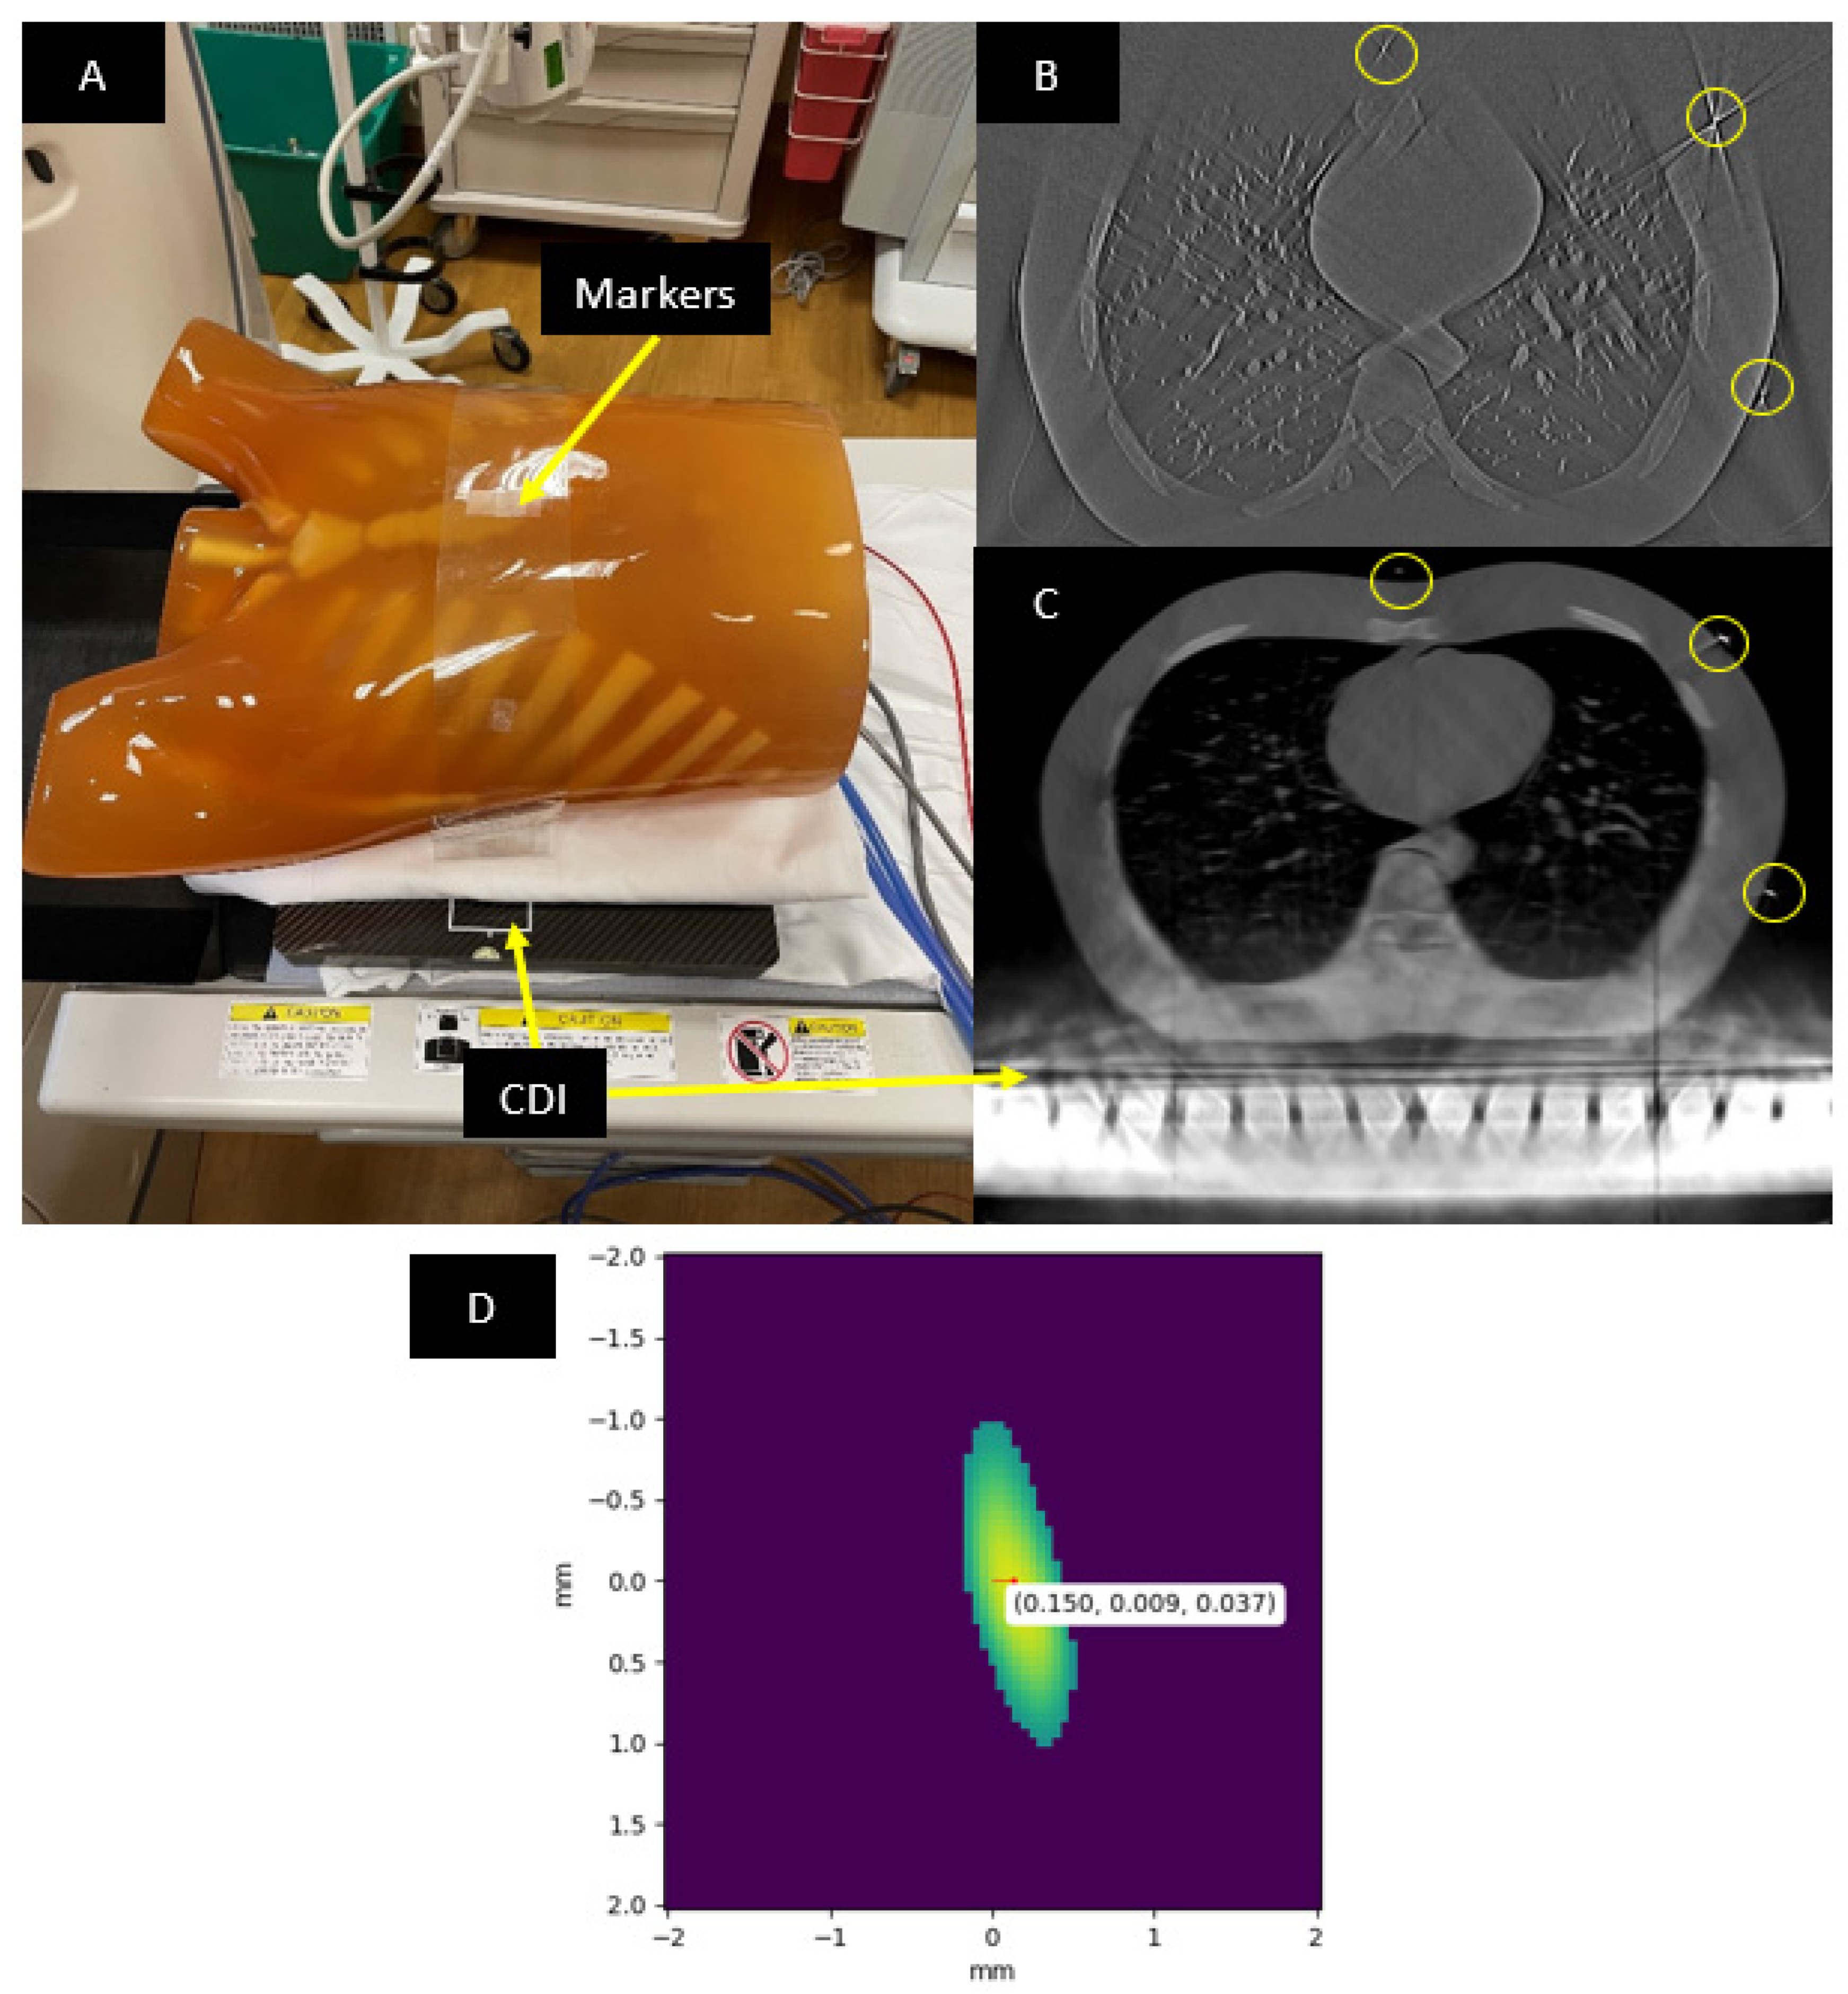

2.1. Imaging Procedure and the Anthropomorphic Phantom

2.2. Initial Estimation of the Geometric Parameters

2.3. Locating the Fiducial Markers in the CT Images

2.5. Evaluation of the Calibration Method Using Blood Vessels